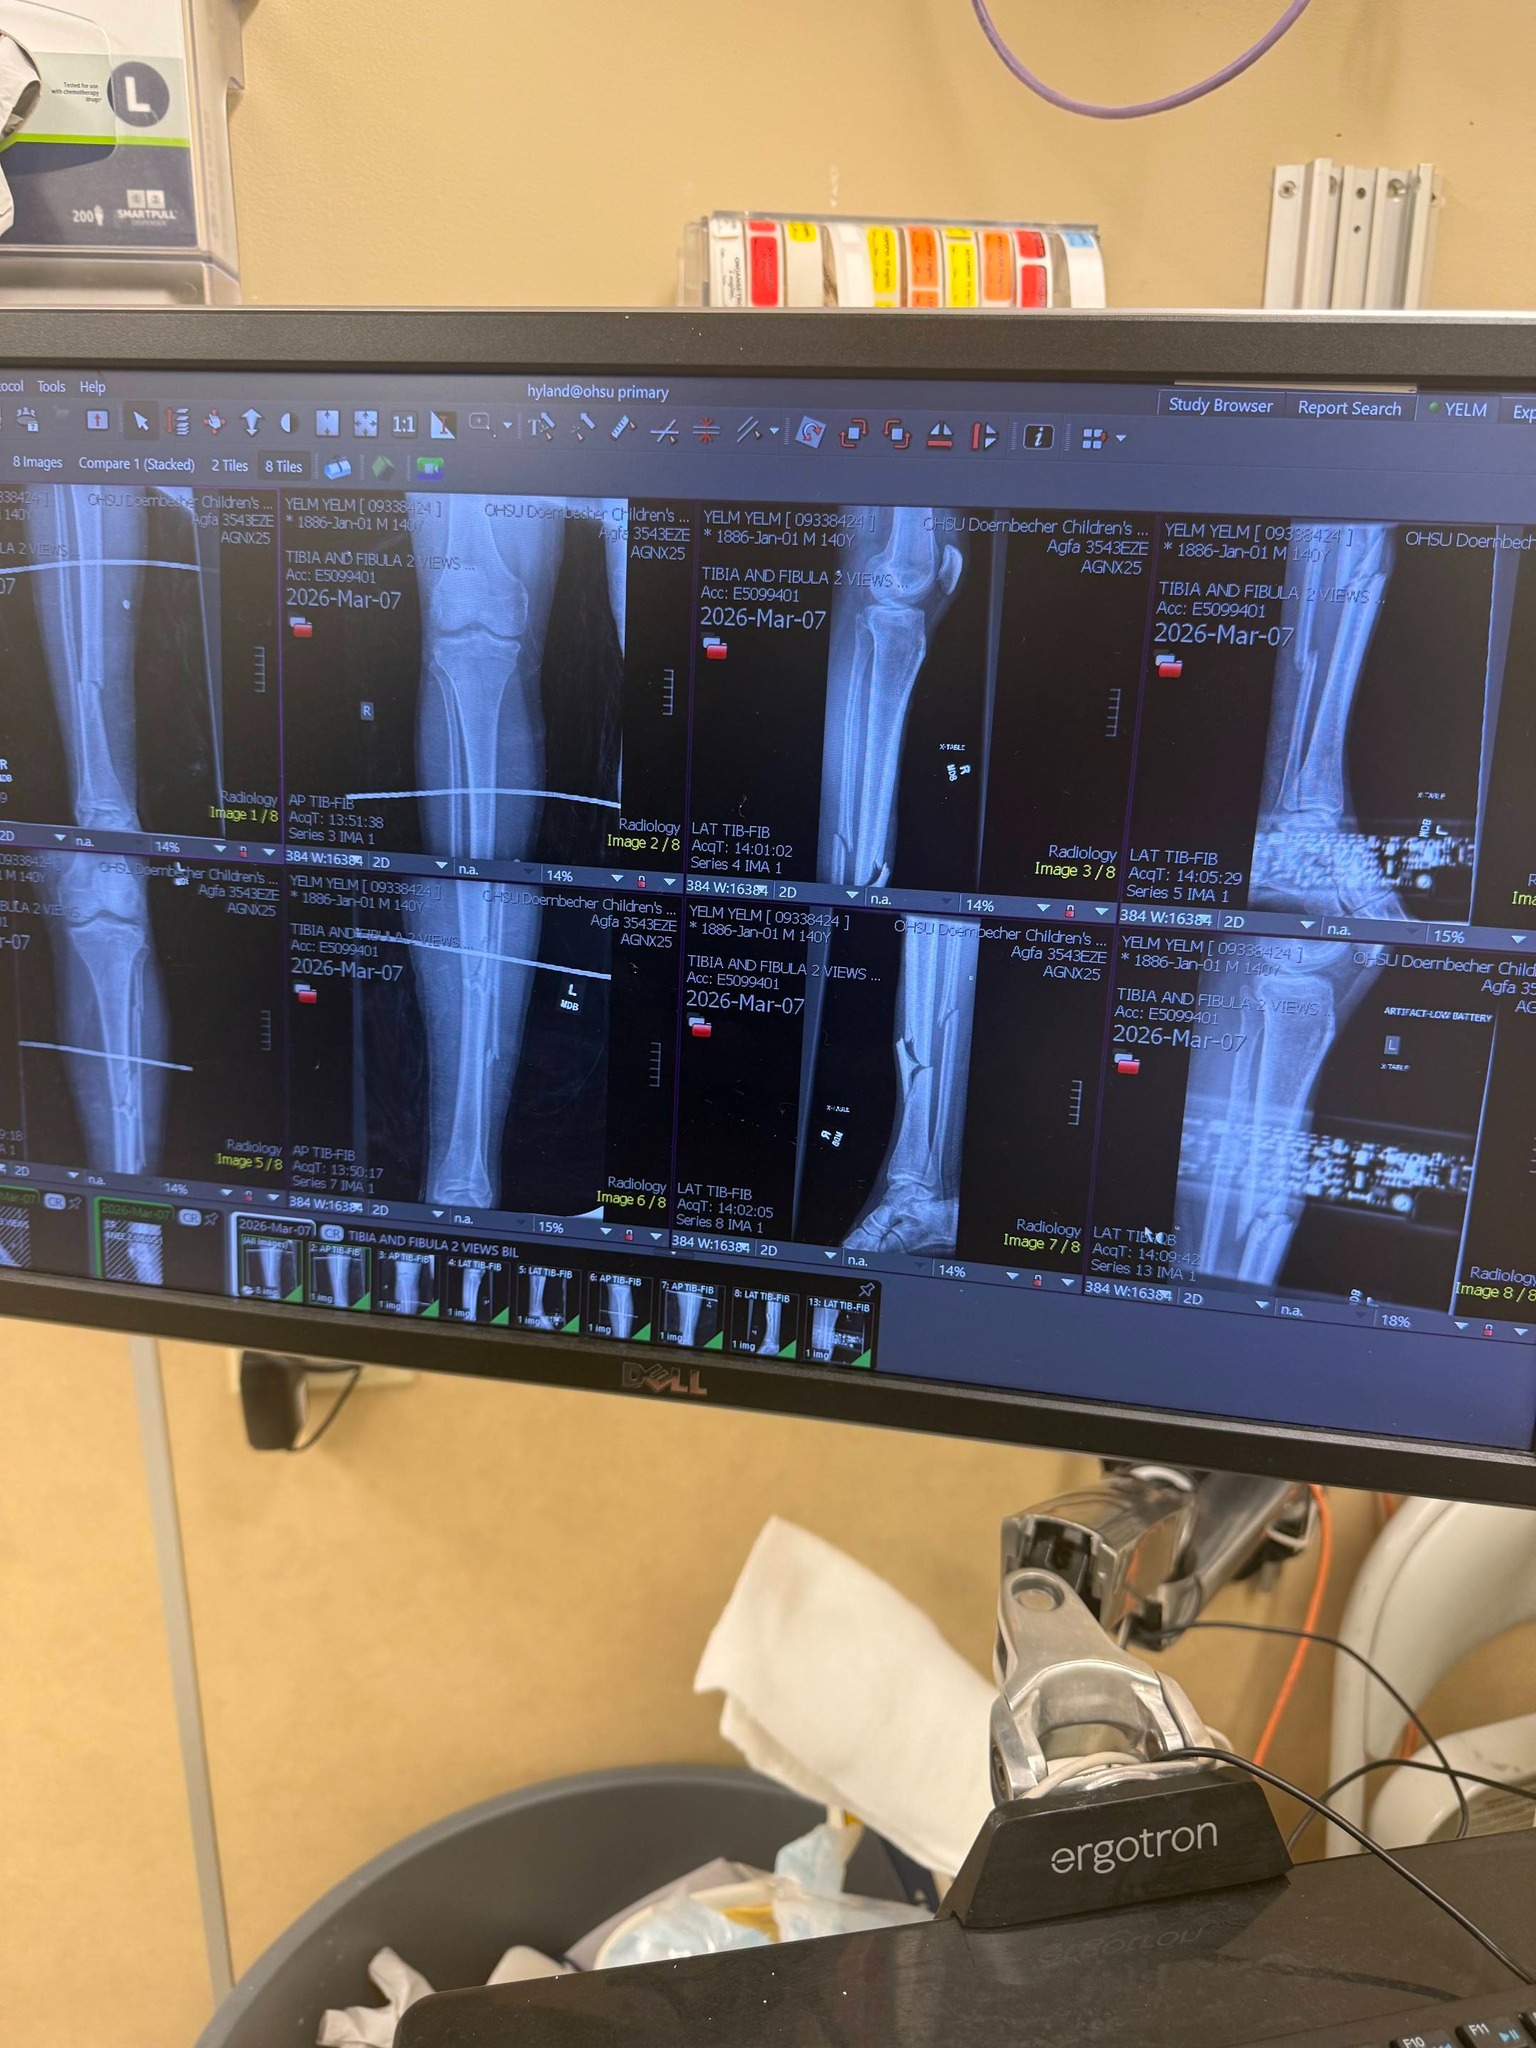

My daughter's boyfriend, Taylor, was in a tragic motorcycle accident, where a car pulled out in front of him, on his way to their gender reveal party on 3/7/26. Taylor was rushed by ambulance to OHSU, where they determined he had broken legs, which he had surgery for today, fractured ribs, collapsed lungs, and other injuries. Taylor is going to have a long road ahead of him in recovery with multiple doctor and physical therapy appointments. Samantha works hard, but she doesn't earn enough to make up for the lost income and extra expenses they will face in the future. I know they would appreciate prayers, shares, and any support you can offer.